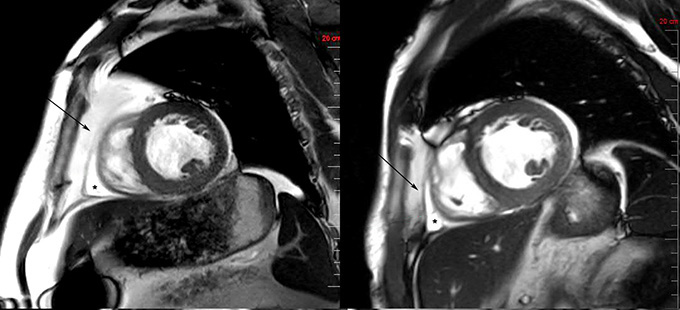

Other results from the SUMMIT tirzepatide trial have starting to capture a picture of what’s happening. MRI images taken before participants started taking the drug show that their hearts are heavy, and also swaddled in fat, Christopher Kramer, chief of cardiology at the University of Virginia in Charlottesville reported at the meeting and in the Journal of the American College of Cardiology. After a year on the drug, heart weight dropped and so did the amount of surrounding fat, Kramer says. “It’s melting away.”